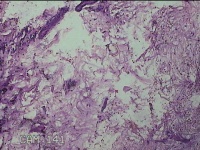

左手指结节

性别

男

年龄

42岁

临床诊断

皮下结节

一般病史

发现左手指结节2个月余。

标本名称

大体所见

灰白粉红色组织1x0.8x0.3cm一块,表面带梭形皮肤1x0.7cm,皮下见结节1x0.8cm,切开皮肤呈实性,切面灰白粉红色,质软。

图片无诊断价值。